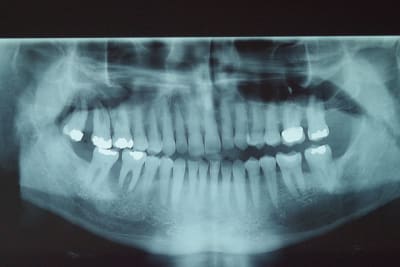

Voilà maintenant les radios:

1° à nouveau une panoramique ( un peu plus haute mais on ne voit pas très bien les ATM )

A priori je ne pense pas que ce patient souffre de luxation au vu des radios.

Qu'en pensez-vous ?